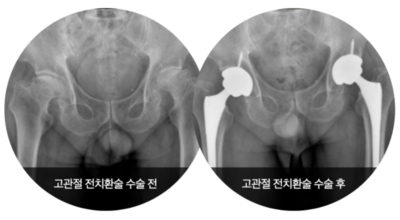

고관절이란 골반을 지탱하는 관절로서 근육과 힘줄로 구성되어 있습니다. 학계에서는 고관절을 엉덩이 관절이라고 부르기도 하며 인체의 하중을 지탱하는 아주 주요한 관절입니다. 각별히 고관절은 우리가 정상적으로 서있거나 움직일 수 있게 만들어주고 달리기, 점프, 무거운 무게를 들 때 최대 체중의 2~10배 가량의 하중을 받기 때문에 적절한 관리가 필요해요. 오늘은 고관절에서 생기게 될 수 있는 고관절 통증 증상에 대하여 알려드릴게요.

고관절염은 고관절에 나타나는 관절염을 말하며 고관절의 연골이 닳게 되면서 뼈와 뼈가 서로 부딪히며 통증을 일으키게 됩니다. 고관절염 초기 증상으로는 사타구니 부위가 불편하게 느껴지며, 무리하면 통증이 생길 수 있다고 하며, 관절염 증상이 심해지면서 사타구니에서 느끼던 통증이 허벅지와 엉덩이 통증으로 이어지기도 하는데, 고관절염 통증 증상으로 초기에는 허리 통증이 나타나 허리 질환과 혼동하기 쉬우며 각별히 척추질환이 있는 사람은 고관절 통증 증상과 마찬가지로 엉덩이, 다리 통증이 동반되기 때문에 훨씬 헷갈리는 경우가 많다고 해요.

나이가 들면 통상적으로 발생되는 질환 중 한 종류입니다. 관절을 지켜주며 있는 연골의 훼손이나 퇴행성 변화로 인해 관절을 이루는 뼈와 인대 등에 훼손이 생겨 염증과 통증이 나타나는 질환입니다. 고관절 쪽 연골이 닳게 되면서 망가지게 되고 또 쉽게 끊이지 않는 통증에 시달릴 수 있습니다.